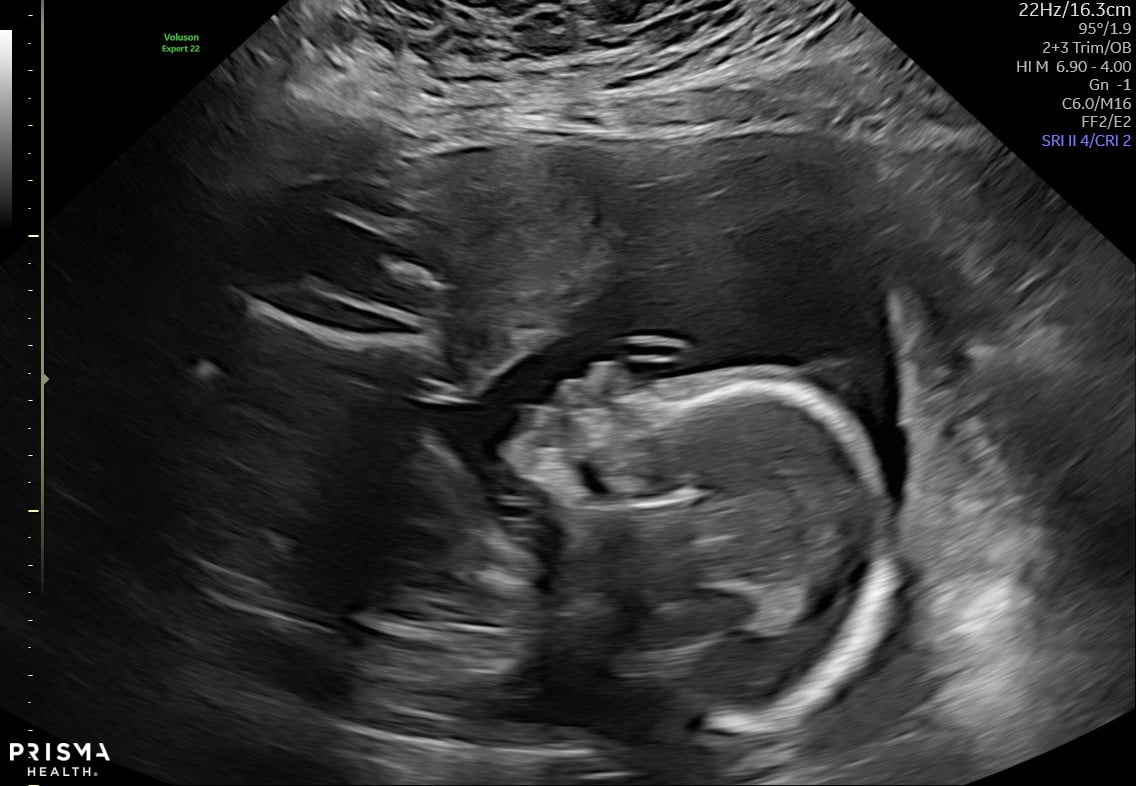

Big yawn, little girl! 20 weeks + 1 day (last Thursday) Estimated about 9 ounces, measuring about a week and a half behind after being right on track earlier in the pregnancy. Placental insufficiency, absent end-diastolic flow, growth restriction... but she was very active during the scan and that is very positive. We'll be doing another scan at 23 weeks and we'll see where we go from there.

Got some amazing news at our followup ultrasound -- I'll post more in the check-in thread. But for now, here's baby girl yesterday at 23 weeks + 1 day.

While I go in for ultrasound twice a week, I don’t often get good images of baby because that’s not the point of the BPP’s and growth scans. But the ultrasound tech I had yesterday did try to get some 3-D shots. Baby girl did not cooperate as she kept tucking her chin and putting her arms in front of her face. 😂 However, I did get a perfect little side profile picture of her.